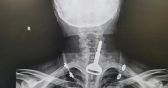

كشفت الشؤون الصحية بالقنفذة عن إجراء فريق طبي عملية تشخيصية وتركيب دعامتين في الشرايين التاجية اليسرى لمريض مصاب بالسكري يبلغ من العمر 54 عامًا، وذلك في مستشفى جنوب القنفذة العام.

وأشارت صحة القنفذة أن المريض حضر إلى الطوارئ يشكو من ألم حاد في الصدر، وقام فريق طبي بالكشف والتشخيص وعمل الأشعة والفحوص اللازمة للمريض.

وأوضحت صحة القنفذة أنه قد تبيّن وجود عدة تضيقات في القلب، وتم التعامل مع الحالة طبيًا وتقديم جميع الخدمات الصحية الملائمة لوضعه الصحي حتى غادر المستشفى بصحة جيدة.